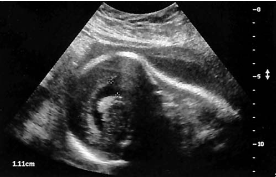

The sonographic finding in this image is most suspicious for:

ventriculomegaly